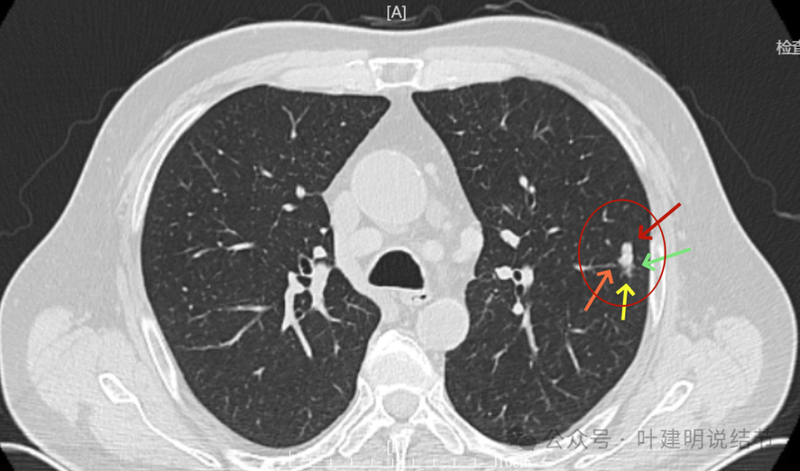

2024年9月再增大进展,见血管进入明显,靠血管这侧的边缘较为毛糙。

局部放大病灶表面不平,血管进入,进入的血管有异常增粗,没有见到明显卫星病灶。

血管与之关系密切,实性密度。

整体有膨胀感,血管有进入病灶。

血管进入明显,边缘毛糙不光滑。

血管进入以及表面不平,形态不规则。